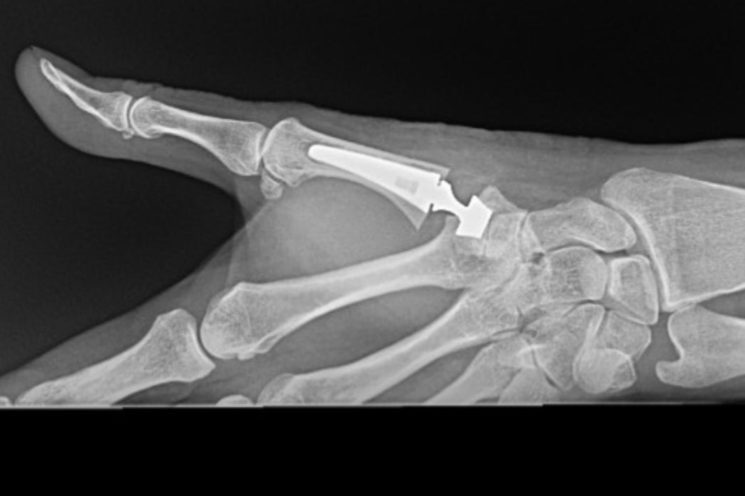

We treat a variety of hand and wrist conditions, including:

- carpal tunnel syndrome

- ganglion

- osteoarthritis

- rheumatoid arthritis

- sports injuries

- trigger finger

Treatments we provide include:

- carpal tunnel release surgery

- Dupuyten’s surgery

- carpometacarpal joint replacement (thumb)